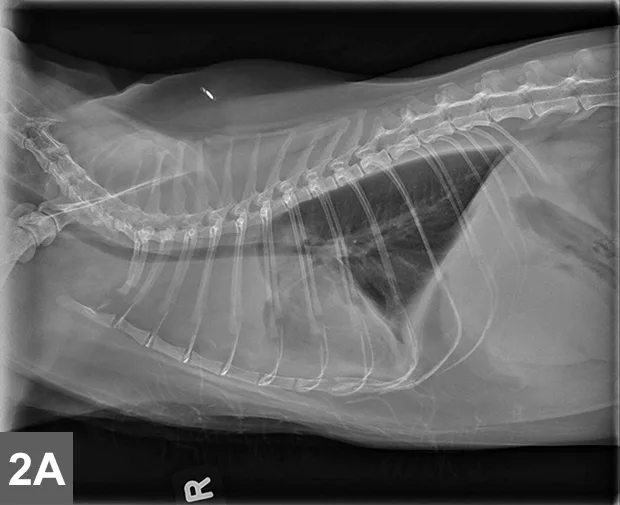

Featured Image

FIGURE 2B

Cranial mediastinal mass in a cat. There is also widening of the cranial mediastinum with rounded margins and border effacement of the cranial margin of the heart in the VD view. Pleural effusion contributes to effacement of the cardiac silhouette and to the widened appearance of the cranial mediastinum in the VD view (arrow).

Mediastinal

• Typically localized form of LSA involves infiltration of the thymus and/or cranial mediastinal and sternal lymph nodes with intermediate to large neoplastic lymphocytes with signs related to the intrathoracic mass effect and secondary pleural effusion (Figure 2).